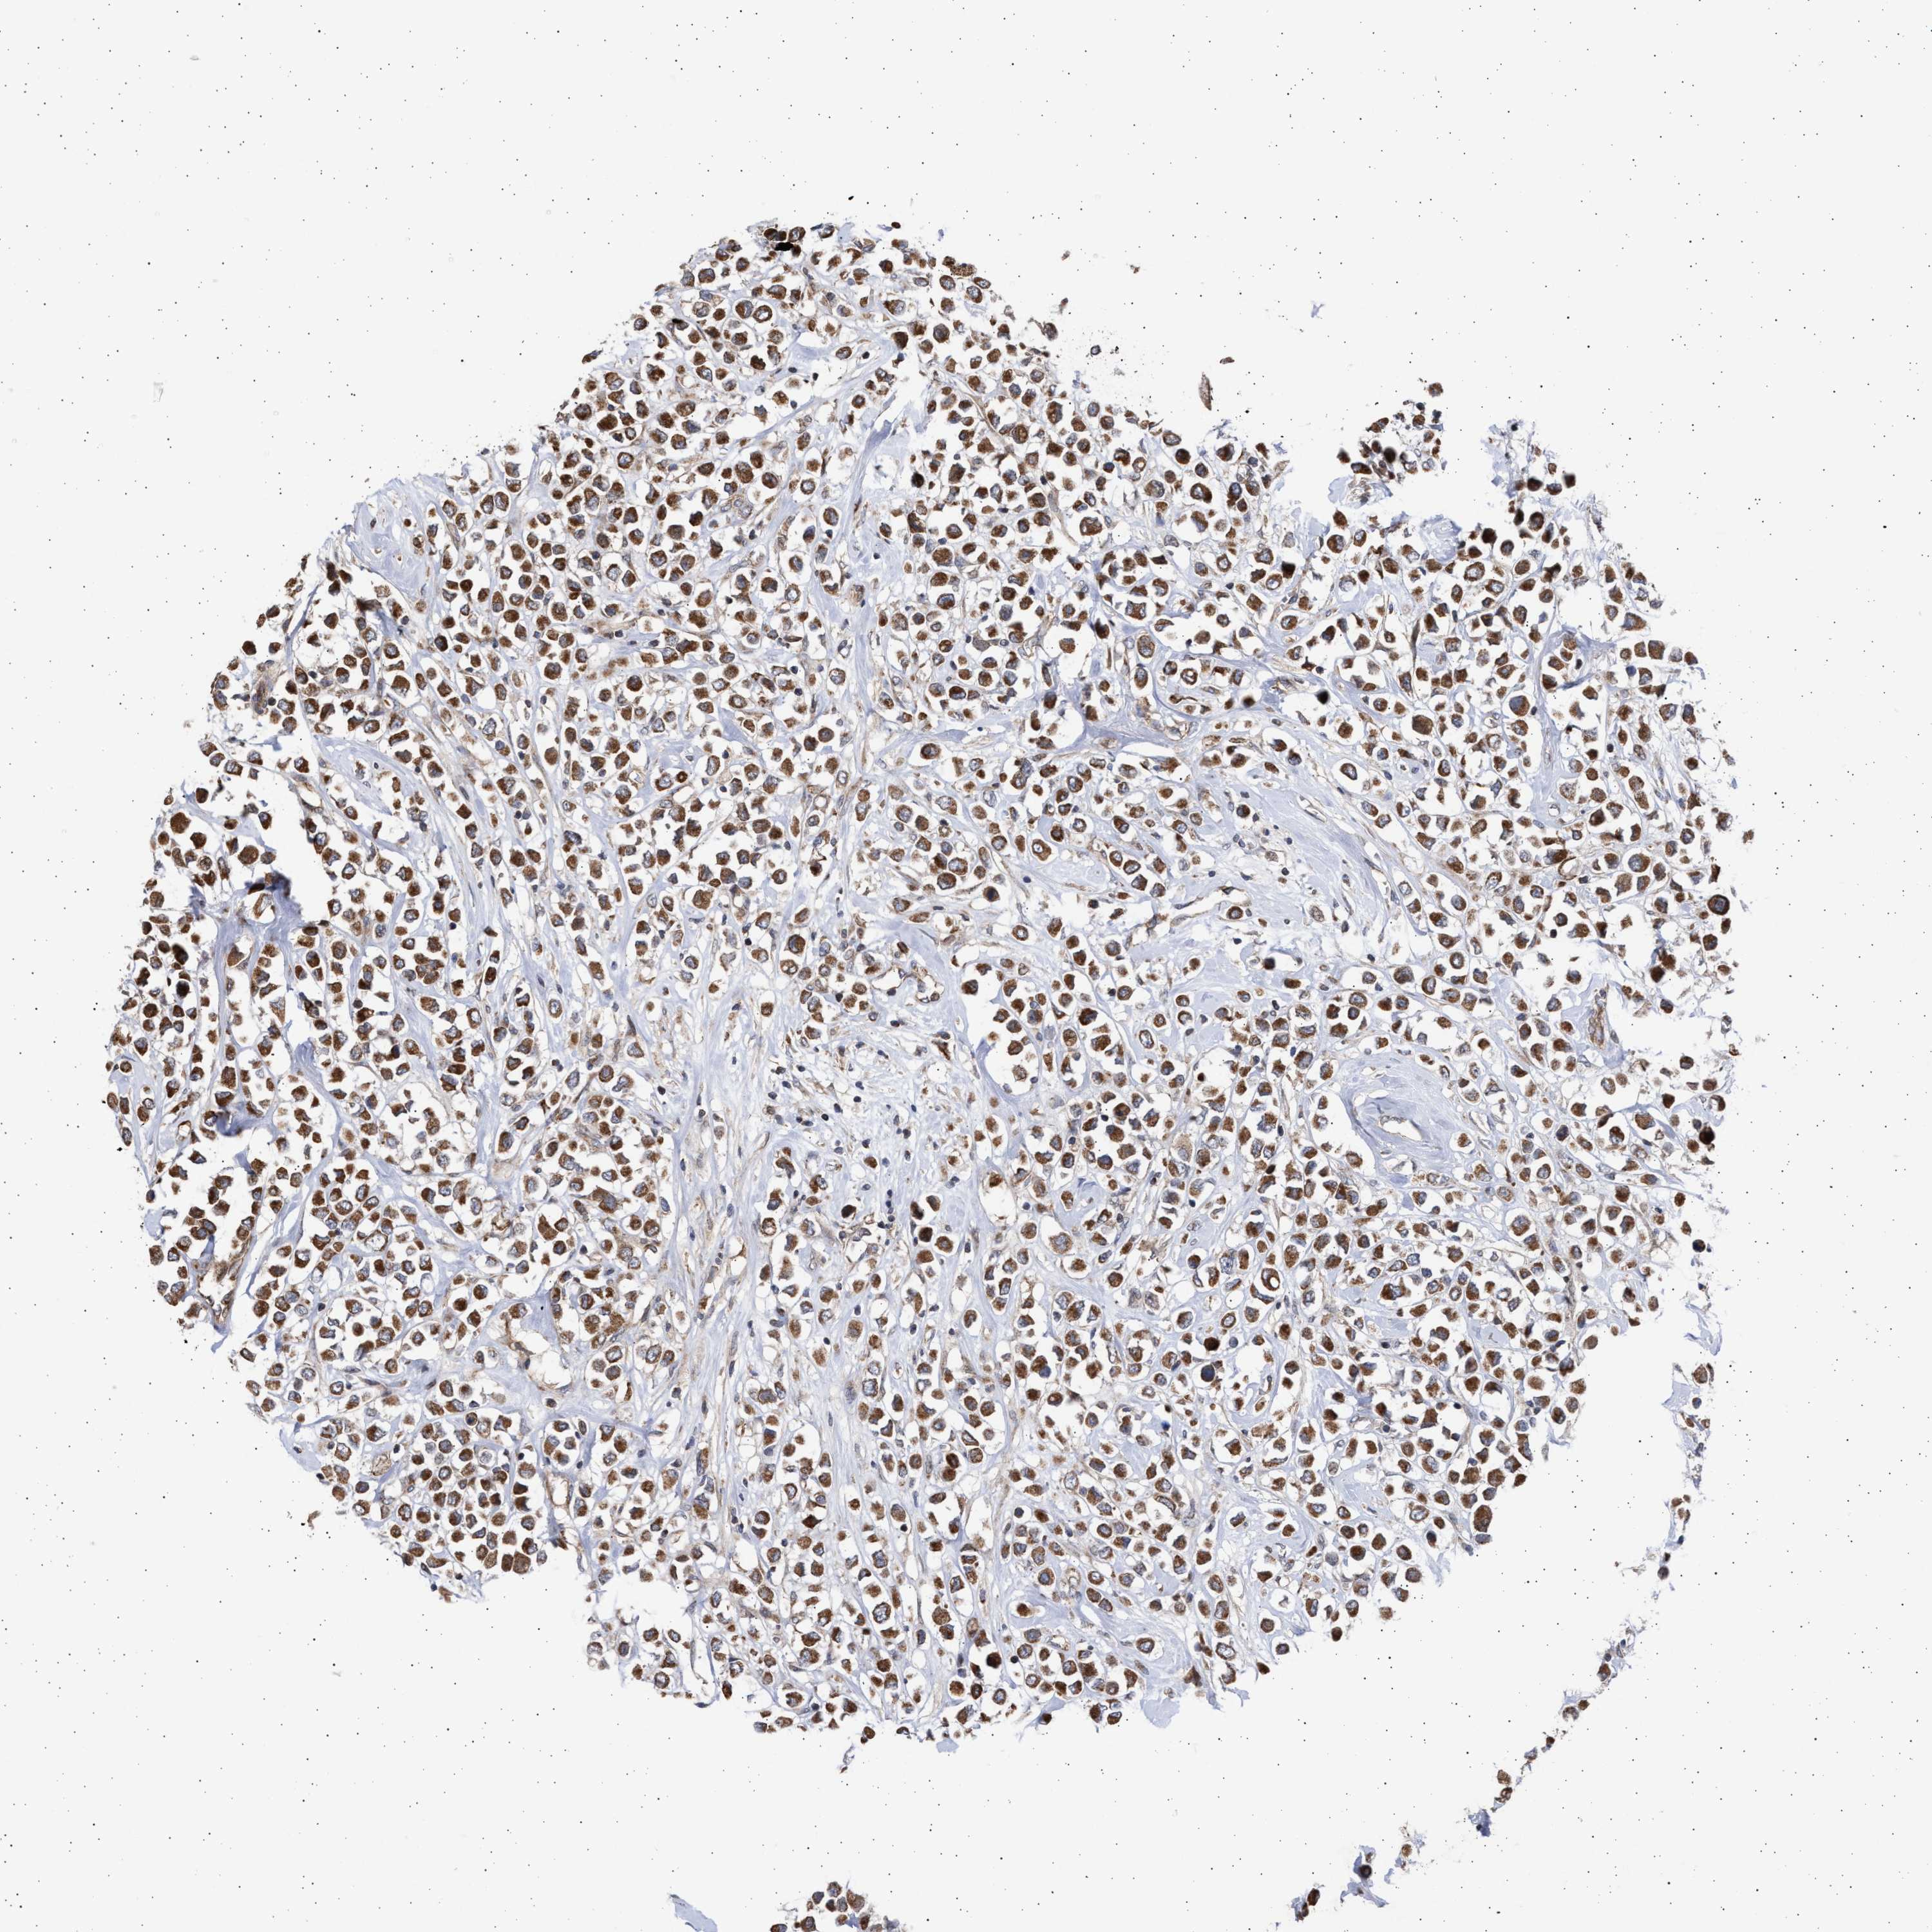

CANCER BREAST CANCER Show tissue menu

BRCA TCGA BRCA VALIDATION PROTEIN EXPRESSION

ANTIBODIES

AND

VALIDATION